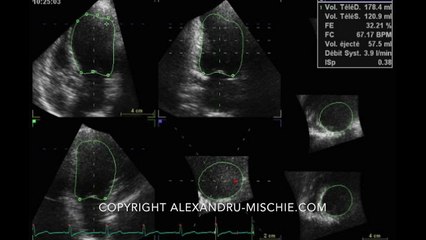

3D LVEF Examples: Left Ventricle Frames

Just a few still frames of 3D ejection fraction of the left ventricle